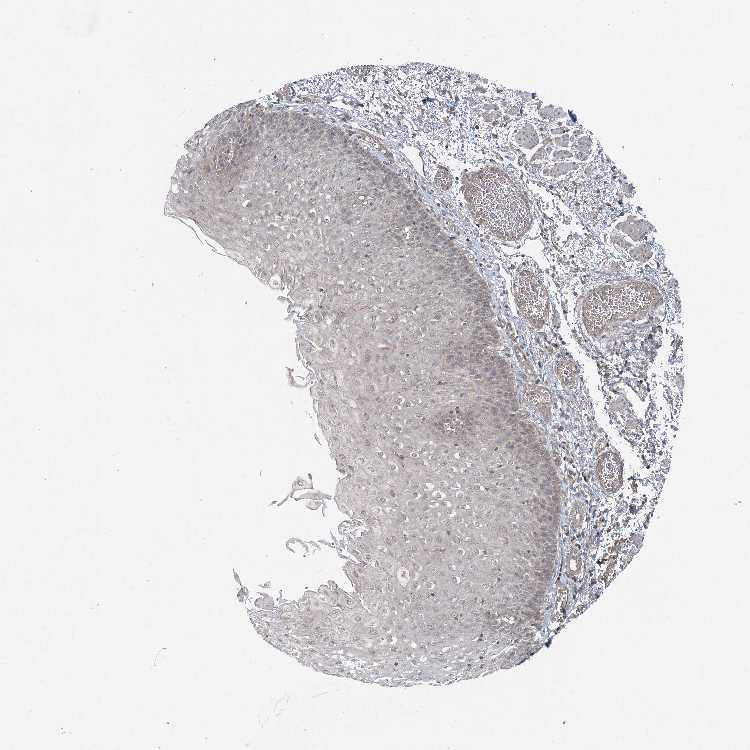

ESOPHAGUS - Antibody stainingi

Antibody staining in the annotated cell types in the current human tissue is reported as not detected, low, medium, or high, based on conventional immunohistochemistry profiling in selected tissues. This score is based on the combination of the staining intensity and fraction of stained cells.

Each image is clickable and will lead to virtual microscopy that enables deeper exploration of all samples and also displays staining intensity scores, fraction scores and subcellular localization as well as patient and tissue information for each sample.

Antibody HPA037905

Squamous epithelial cells Low